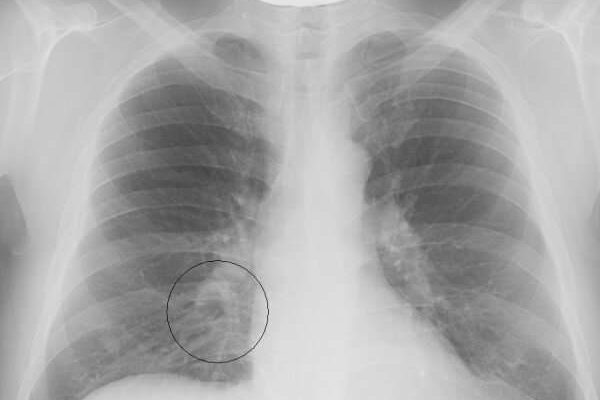

Выделение патологии в отдельную группу оправдано тем, что она имеет специфические диагностические, клинические и прогностические свойства. Этот тип пневмонии сложно визуализировать на рентгеновских снимках, потому что локализация похожа на корень легкого.

Наличие пневмонии в организме ребенка можно подтвердить только после рентгенологического исследования и проведения лабораторных исследований. Если диагностирована колющая пневмония, необходим дифференциальный диагноз, чтобы отличить эту патологию от туберкулеза и онкологии бронхов.

1. Рентген. На фото виден затемненный участок.